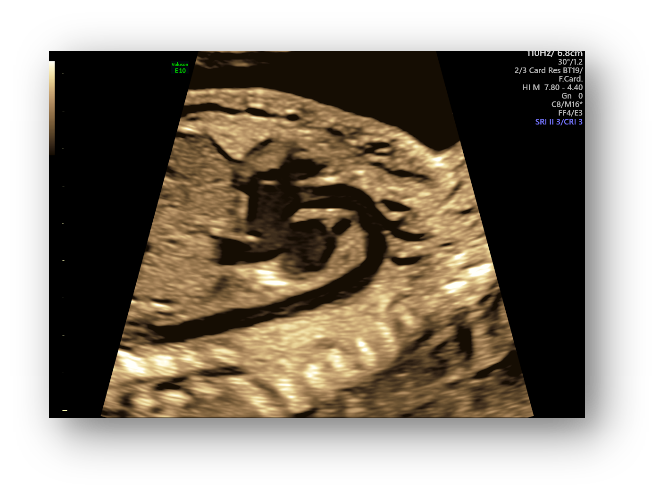

借助自动化技术可进行胎儿颈项透明层、颅内透明层的精准测量,

评估早孕期胎儿染色体异常的风险,对中孕期开放性脊柱裂的风险进行预测。

SonoNT™/SonoIT

颈项透明层/颅内透明层的厚度测量

FMF认证